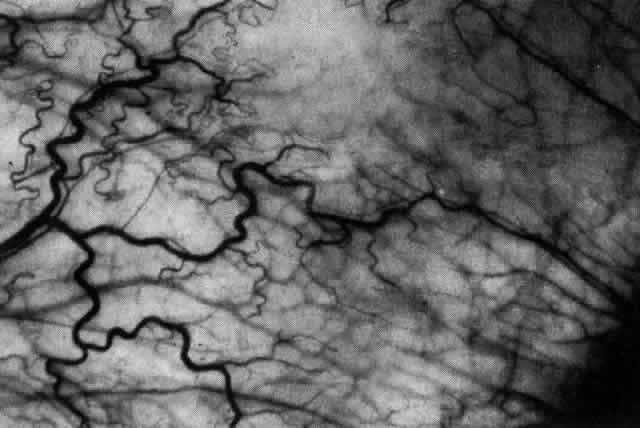

What is clinically represented solely by inflammation and edema is histopathologically a granulomatous lesion of the sclera, the center of which consists largely of plasma cells, lymphocytes, and mast cells (Figs. 21 through 23). Foster and colleagues have identified the cellular subsets and glycoproteins in both necrotizing and non-necrotizing scleritis.22 This shows an active T-cell inflammatory response with a high CD4/CD8 ratio and increased HLA/DR and CD14, indicating a macrophage-induced response that would lead to granuloma formation. Remote from the granuloma, the fibrocytes of the sclera become activated, the proteoglycan adjacent to them becomes altered, and the collagen fibrils of the sclera become unraveled (Figs. 23 and 24). These changes appear to take place prior to the invasion of the stroma by cells of the granuloma.20 The vessels in and around the necrotic area show medial necrosis and perivascular cuffing with lymphocytes, and endothelial swelling with microvascular occlusion. Ninety-six percent of the specimens examined by Foster and associates show a microangiopathy characterized by a neutrophil infiltrate in and around the vessel wall.22–23 This is most obvious at the center of the lesion where there may be occlusion of the vessel, thrombosis, or even aneurysm formation (Fig. 25). From these pathologic investigations, clinical observations, animal experiments, and the results of fluorescein angiography, it would appear that the scleral inflammation is initiated either by trauma (be it accidental or surgical)23–25 or by bacterial or viral infection. If circulating immune complexes are present because of the poor blood flow, they become precipitated in and around the vessel walls in the area of inflammation. In other patients, a persistence of tissue damage will lead to autoimmunization. Damage to the endothelial cells of the microvasculature leads to changes within the vessels detectable on angiography and to catabolic changes in the surrounding tissues. These changes, in turn, allow the granulomatous response that is seen in histopathologic sections, the first detectable change being in the scleral fibrocytes and the proteoglycan and collagen remote from the site of cellular infiltration.

Fig. 21. Advancing edge of a granulomatous reaction. Scleral fibers are split and separated by edema and then disrupted when invaded by the granuloma

Fig. 22. Electron micrograph of an area of active scleritis showing the plasma cell infiltrate suggestive of an immune response. Note aggregated plasma cells, with the characteristic whorled rough endoplasmic reticulum, in the process of degeneration, releasing organelles and nuclear debris into the extracellular matrix. (Uranyl acetate and lead citrate. X3000) (Courtesy of Dr. R. Tripathi)

Fig. 23. Electron micrographs of scleral stroma at the periphery of an area of ulceration in a patient with necrotizing scleritis. The left shows an active fibroblastic cell, and the right shows collagen fibrils within intracellular vacuoles (V) in the fibroblastic cell. (Left X15,375; right X15,375) (Watson PG, Young RD: Changes at the periphery of a lesion necrotizing scleritis: Anterior segment fluorescein angiography correlated with electron microscopy. Br J Ophthalmol 68:781–789, 1984)

Fig. 24. Electron micrograph of scleral stroma at the periphery of an ulcer in necrotizing scleritis (same patient as in Figure 23) showing swelling and unraveling of collagen fibrils (arrows) in longitudinal section (X29,270) and in transverse section (inset, X44,000). Fibrils of all diameters are affected. (Watson PG, Young RD: Changes at the periphery of a lesion necrotizing scleritis: Anterior segment fluorescein angiography correlated with electron microscopy. Br J Ophthalmol 69:656–663, 1985)

Fig. 25. Intense lymphocytic reaction and infiltration around a medium-sized arteriole and nerve.